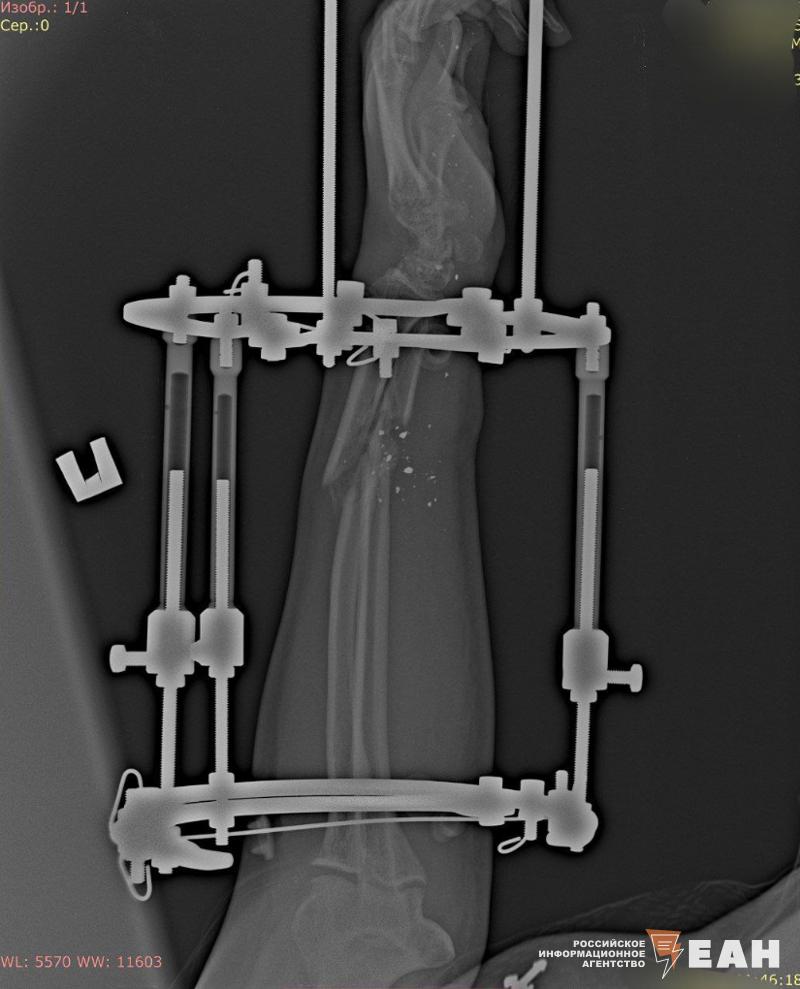

29 октября он получил третье ранение, причем в ту же руку – у него огнестрельное ранение с открытым переломом предплечья. Его сразу направили в госпиталь в Ростов, откуда 2 ноября отправили санитарным поездом, который курсирует по Поволжью, но нигде Алексея не могли сдать в госпиталь. После публикации ЕАН сына и еще часть раненых из этого госпиталя привезли в Екатеринбург», - рассказала ЕАН мать солдата.

После ранения у Алексея Шаталова началась гангрена кисти, и врачи уже были вынуждены ампутировать фалангу большого пальца на руке. Ольга Шаталова, которая сама медик, военный фельдшер, сказала, что очень хорошо понимает, что чем раньше начнется лечение, тем больше шансов на выздоровление и спасение руки.